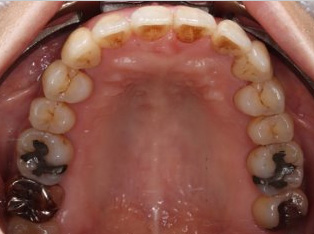

乱ぐい歯、でこぼこがとても酷い状態になります。歯が前後的に重なってしまっている、八重歯になっているなどがこのジャンルに入ります。

顎の大きさと歯の大きさのギャップが大きく、時には歯を抜かないと矯正治療ができない場合もあります。当院では治療期間が長くなるが抜かない治療方針など、一つの治療プランだけでなく、さまざまな可能性の治療方針を説明させて頂くよう心掛けております。こういった考え方はインフォームド・チョイスと言われ近年大切にされている考え方と言われております。

治療前

治療終了前